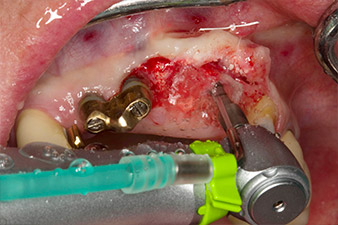

orificio piloto utilizando el nuevo Implantmed y el contra-ángulo WS-56 L

Imagen 2: Dos meses después, se practicó un orificio piloto utilizando el nuevo Implantmed y el contra-ángulo WS-56 L (programa P1, transmisión 1:1). La refrigeración se realizó a través del tubo de spray colocado a la izquierda (para diestros).